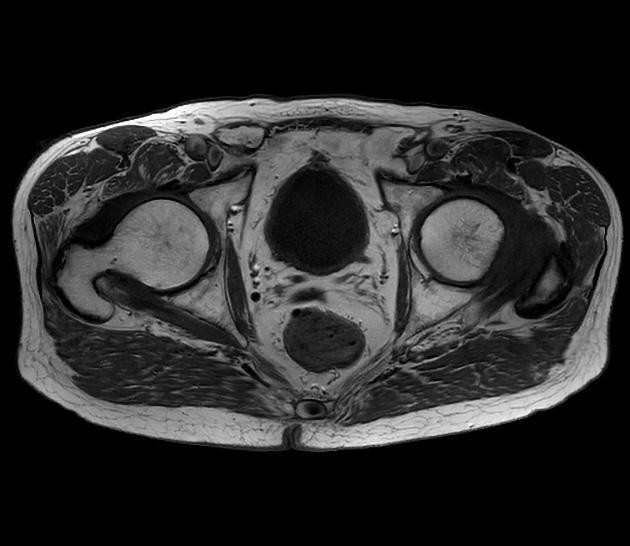

Pre úspešnú liečbu rakoviny prostaty je kľúčová včasná a správna diagnostika, ktorá sa skladá z viacerých po sebe nasledujúcich vyšetrení, medzi ktoré patrí stanovenie osobnej a rodinnej anamnézy pacienta a fyzikálne a biochemické vyšetrenie. Biochemické vyšetrenie je zamerané na vyšetrenie prítomnosti PSA (prostata špecifického antigénu) v krvi. Ide o bielkovinu, ktorá je produkovaná prostatou a následne je vylučovaná do krvi. V prípade pacientov s karcinómom prostaty je hodnota PSA vyššia ako je fyziologická norma. Na základe hodnôt PSA je možné rozdeliť pacientov na základe stupňa progresie ochorenia. Vyšetrenie hladiny PSA v krvi však nie je definitívne pri určovaní diagnózy, keďže zvýšené hodnoty sú prítomné aj pri iných ochoreniach, preto je potrebné ďalšie urologické vyšetrenie. Fyzikálne vyšetrenie u urológa pozostáva z palpačného vyšetrenie per rectum, kedy je prostata pri karcinóme zväčšená a sú prítomné tuhé uzly. V prípade nálezu uzlov je pacient odoslaný na doplňujúce vyšetrenia ako sú transrektálna sonografia alebo magnetická rezonancia. Okrem týchto vyšetrení je pre určenie diagnózy potrebná aj biopsia prostaty, kedy sa ihlou odobraná vzorka tkaniva prostaty sleduje pod mikroskopom a patológ pozoruje výskyt nádorových buniek vo vzorke.

Pre určenie optimálnej liečby rakoviny prostaty je potrebné určiť rozsah ochorenia. Štádium ochorenia sa určuje formou tzv. TNM klasifikácie, kde kategória T znamená rozsah postihnutia samotnej prostaty rakovinovým nádorom, kategória N určuje metastatické postihnutie panvových lymfatických uzlín a kategória M opisuje prítomnosť (resp. neprítomnosť) vzdialených metastáz. Takéto informácie nám vie poskytnúť magnetická rezonancia, histologické vyšetrenie odstránených lymfatických uzlín či rádioizotopová gamagrafia kostného systému, ktorou sa zisťujú známky metastatického postihnutia skeletu. Pri rozhodovaní o spôsobe liečby lekári berú do úvahy viaceré parametre – histologický charakter nádoru, hodnota PSA, vek pacienta a jeho celkový zdravotný stav.